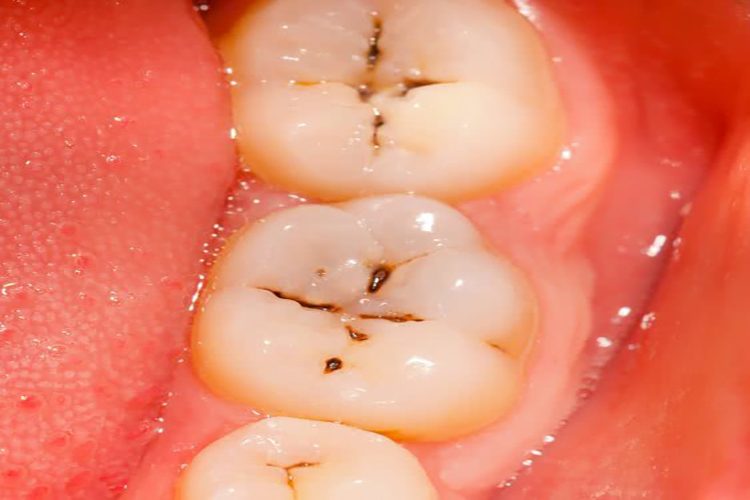

龋齿

龋齿的临床表现为窝沟部位变黑,平滑面一般呈白垩色、黄褐色或褐色斑点,也可出现牙齿上有一条一条的黄线,遇到冷、热、酸、甜等刺激时,牙齿疼痛。

龋齿是一种多因素疾病,是口腔微生物、碳水化合物、敏感的宿主和食物四个因素相互作用的结果。

龋齿的治疗是终止龋损的发展,修复牙的形态与功能。可采用再矿化、预防性树脂充填等技术,终止或消除龋齿。